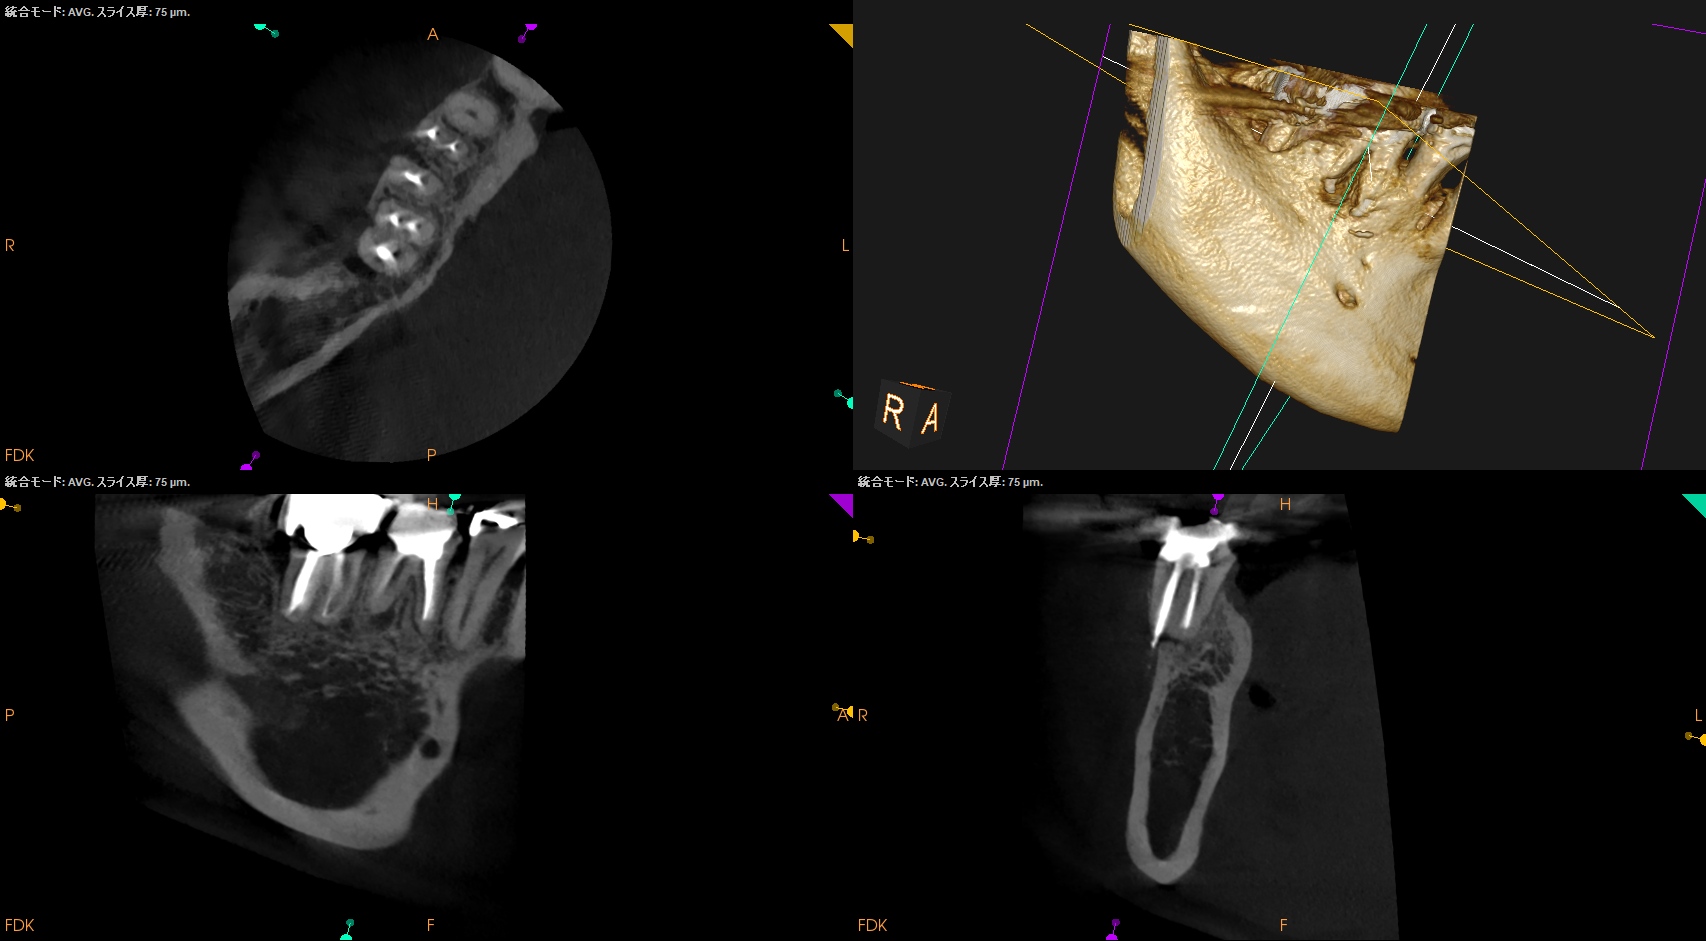

術後にPA, CBCTを撮影した。

#30

MB

ML

D

かかりつけ医にはプロビジョナルレストレーションの装着を依頼した。

次回は半年後である。